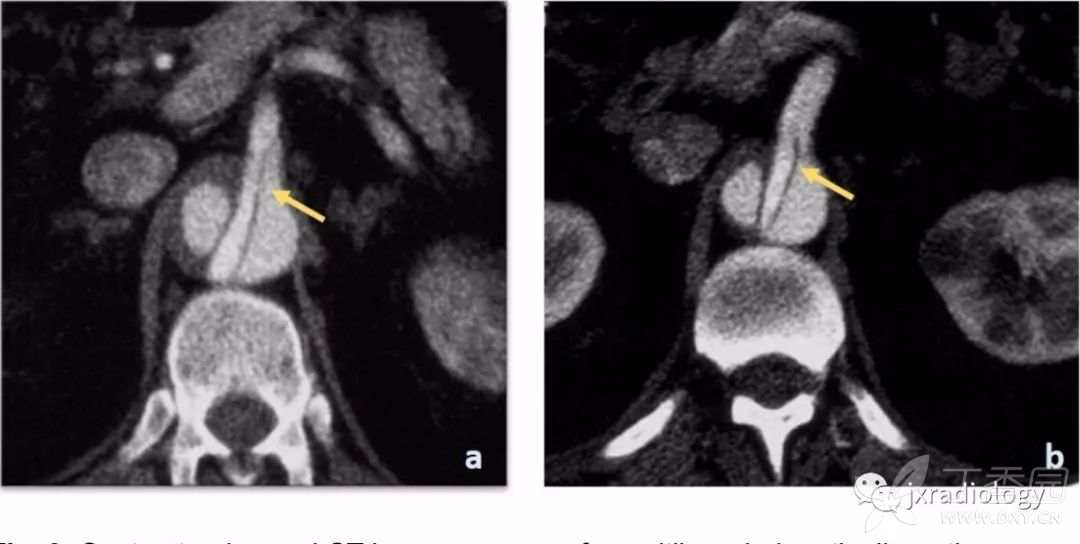

图9:增强CT显示罕见的多腔型主动脉夹层的病例。

可见两个假腔,内膜瓣延伸至腹腔干(a图箭头所指)和肠系膜上动脉(b图箭头所指)。